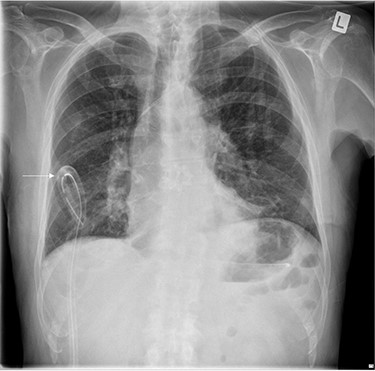

The left basal chest drain was removed without incident on Day 5. However, the nurse encountered resistance during attempted removal of the right basal chest drain. The intern was subsequently notified. Resistance was also encountered by the intern during a further attempt to remove the chest drain. A chest X-ray performed earlier in the day was reviewed (Fig. 2). It demonstrated kinking of the drain around a rib. The intern altered the direction of traction in order to account for the kinking but, during gentle traction, the chest drain fractured at the 14-cm mark (Fig. 3) and became retained within the right hemithorax (Fig. 4). The thoracostomy wound was closed and senior help was immediately sought.

Chest X-ray demonstrating kinking of the chest tube around a rib on the right side.